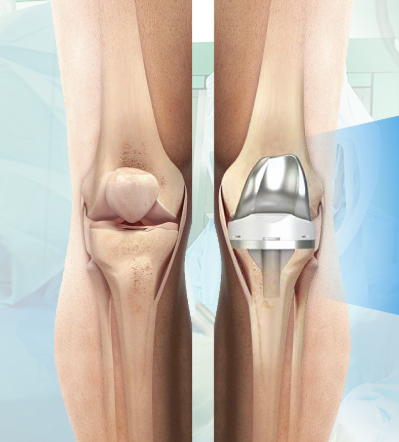

1. 무릎 인공관절 수술이란?

무릎 인공관절 수술은 퇴행성 관절염이나 관절 손상으로 인해 정상적인 생활이 어려운 분들을 위해 손상된 관절을 금속 또는 플라스틱 인공관절로 치환하는 수술입니다.

- 일반적으로 치환술이라고도 하며, 전치환(전체 교체)과 부분 치환술로 나뉩니다.